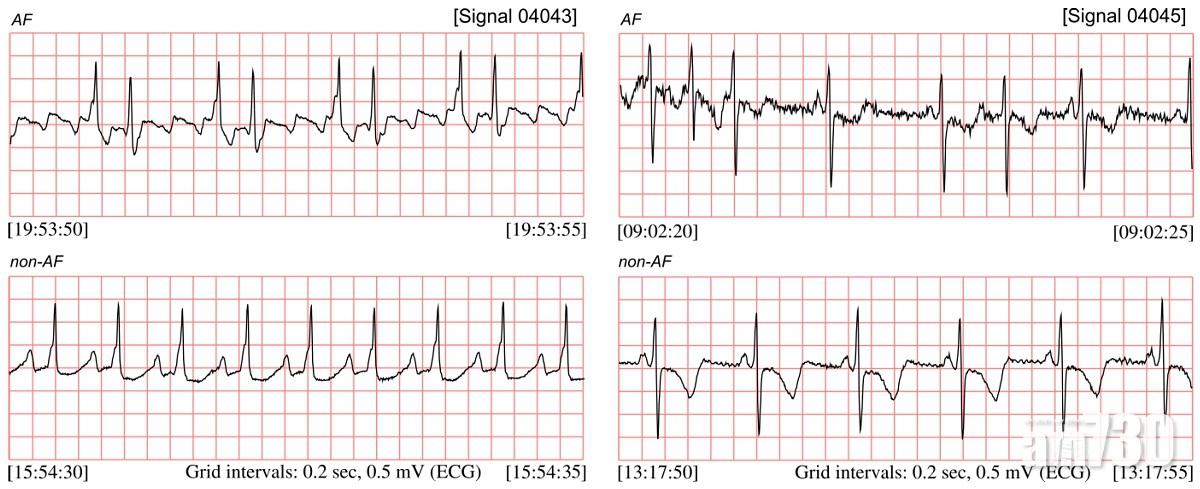

心律不整問題可經心電圖檢測出來。